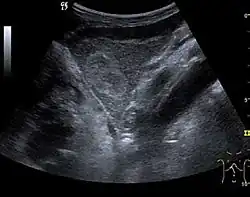

Liver abscess (2D and CEUS). 2D Examination reveals the fluid nature of the mass and imprecise delineation. CEUS examination shows congestion in the surrounding liver parenchyma and excludes a vascular tumor.

Liver abscess have heteromorphic ultrasound appearance, the most typical being that of a mass with irregular shapes, fringed, with fluid or semifluid content, with or without air inside. Doppler examination shows the lack of vessels within the lesion. CEUS exploration shows hyperenhancement during arterial phase close to the lesion, this being suggestive of a liver parenchymal hyperemia. During venous and sinusoidal phase the pattern is hypoechoic, and the central fluid is contrast enhanced. CEUS examination is useful because it confirms the clinical suspicion of abscess. In addition, it allows for an accurate measurement of the collection size and an indication regarding its topography inside the liver (lobe, segment).